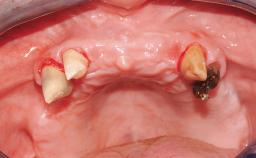

A fully edentulous 65-year-old woman was referred to our clinic for esthetic and functional dental rehabilitation. The patient presented with inadequate complete maxillary and mandibular prostheses, insufficient vertical dimension, and extensive tooth wear. The clinical examination and anamnesis showed no local or systemic contraindications, no signs or symptoms of bruxism, and an absence of smoking habits. The treatment proposed was implant placement in the mandibular interforaminal area and immediate loading with a fixed definitive prosthesis. A removable mucosa-supported complete prosthesis was indicated for the upper jaw, since its bone structure offered satisfactory retention and the financial condition of the patient disfavored a full-mouth implant-supported rehabilitation.